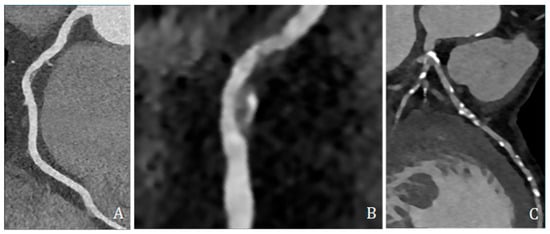

Figure 3.

3D reconstruction of coronary CT angiography showing a significant stenosis in the proximal segment of the left anterior descending coronary artery.

High-risk plaque features were assessed and included low-attenuation plaque (LAP, ≤30 HU), spotty calcification (SC, dense foci > 130 HU within non-calcified tissue and <3 mm), and positive remodeling (PR, remodeling index ≥ 1.1) (Figure 4).

Figure 4.

Coronary CT angiography showing different plaques and morphologies along different coronary arteries. (A,B) show predominantly non-calcified plaque, with low density, positive remodeling, and spotty calcification; (C) shows several predominantly calcified plaques all along coronary arteries, mainly the left anterior descending artery.